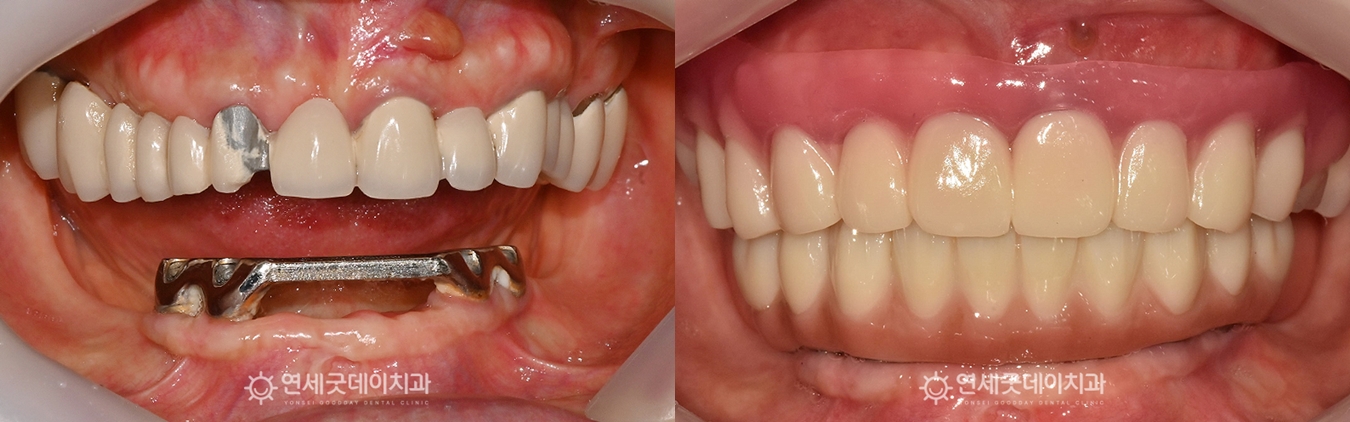

▲ 상악 진행중, 하악 치료 종결 (촬영시기 : 2025년 12월)

하악 All-on-X 치료가 마무리되었습니다.

잇몸이 눌리는 부위는 없는지, 틀니의 모양과

교합은 이상적인지 등 정교하고 세심하게 점검하였으며

내면까지 안정적으로 잘 맞는 상태임을 확인하였습니다.

▲ All-on-X 전체임플란트 치료후 (촬영시기 : 2025년12월)

치료 후에는 이전보다 훨씬 편해지고, 심미적으로 개선되었다며

환자분께서도 높은 만족감을 표현해주셨습니다.

현재 상악은 임시 틀니를 제작해드린 상태이며

약 3개월 후 All-on-X 치료를 이어서 진행할 예정입니다.

▲ All-on-X 전체임플란트 치료전후

(촬영시기 : 2025년11월 / 2025년12월)

심미성 개선은 물론 자연치아에 가까운

우수한 고정력과 안정적인 저작력을 기대할 수 있는 결과를 얻었습니다.